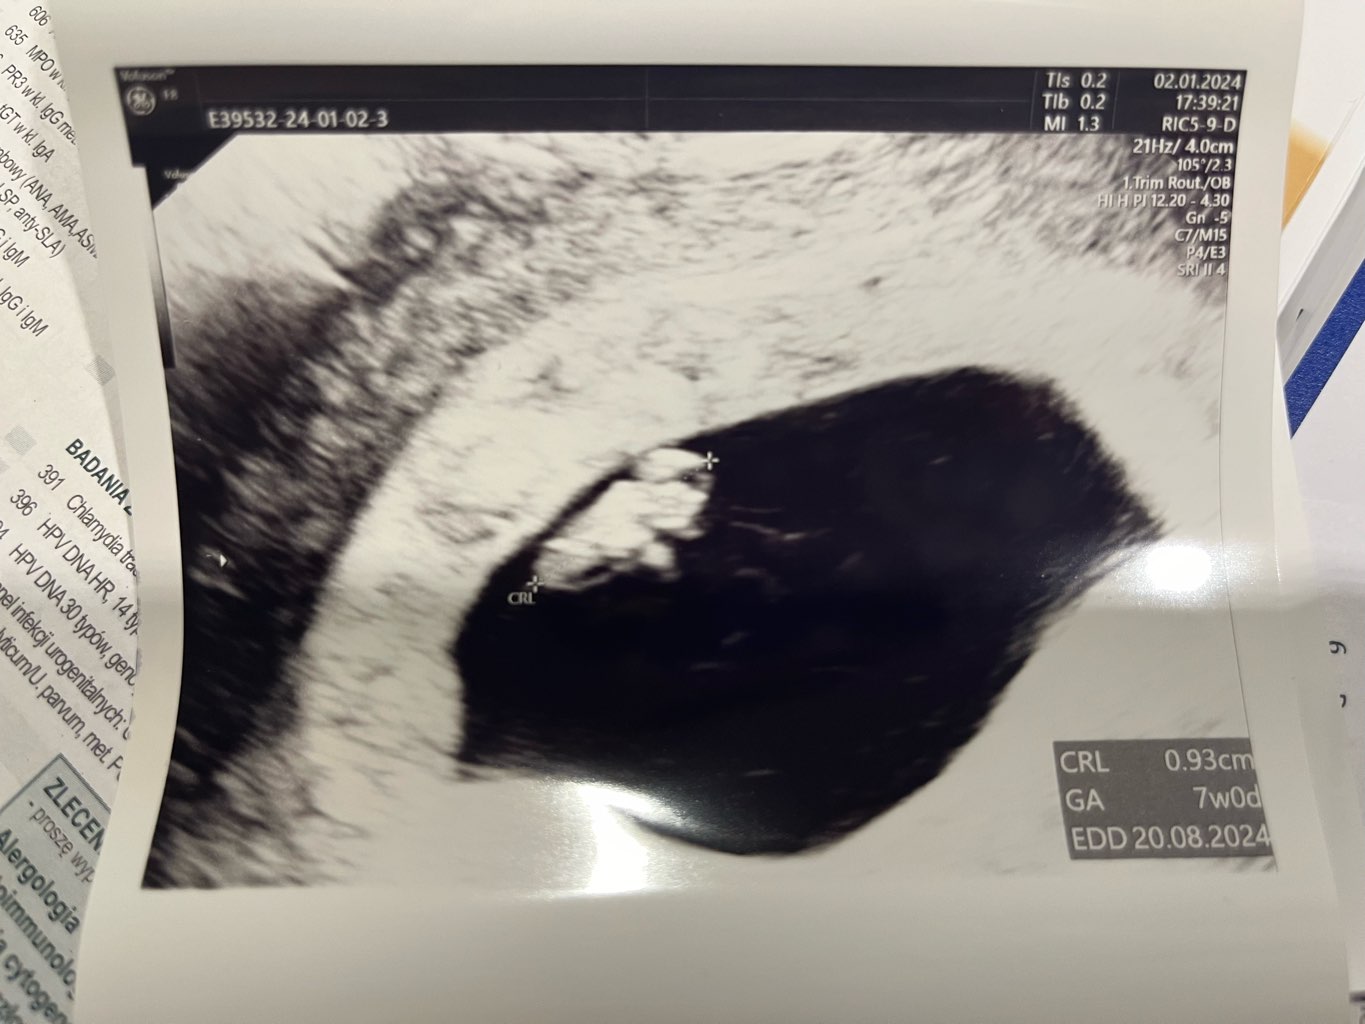

Jestem po wizycie. Wszystko w najlepszym porządku

dzidziuś ma już 0,93cm

i znów jakby o 1 dzień przyspieszył